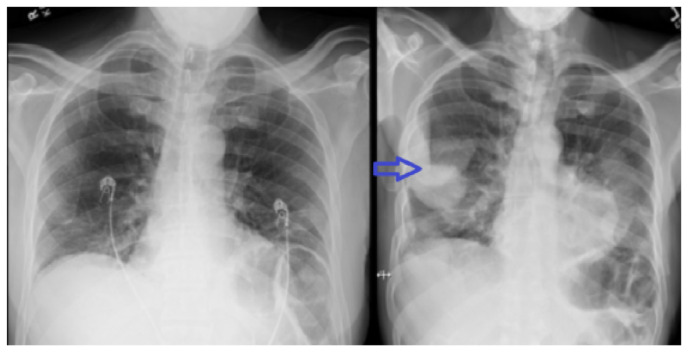

Streptococcus pyogenes is a rare cause of empyema, especially in immunocompetent individuals. The organism expresses various virulence factors leading to rapid progression of the disease. We report a case of rapidly progressing bilateral loculated empyema caused by streptococcus pyogenes in an immunocompetent host without additional risk factors.